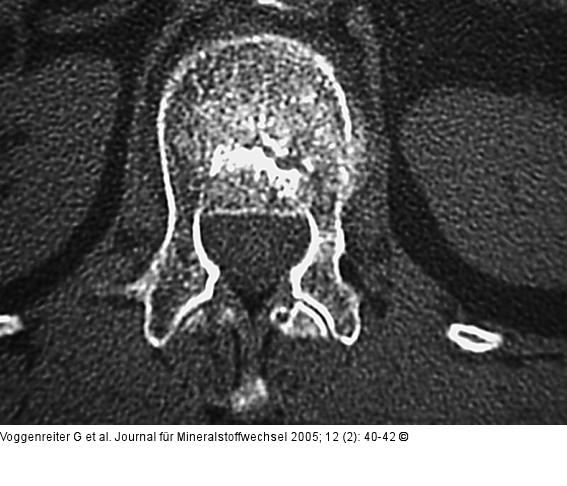

Abbildung 4a-d: Wirbelkörperaufrichtung - postoperative Darstellung Postoperative Darstellung der Zementverteilung und der Wirbelkörperaufrichtung im CT. Trotz Beteiligung der Wirbelkörperhinterkante kam es zu keiner weiteren Einengung des Spinalkanals, sondern durch Ligamentotaxis eher zu einer Erweiterung. Das postoperative Kontroll-CT zeigt eine Reduktion der Kyphose bei klinischer Beschwerdefreiheit der Patientin. |

Postoperative Darstellung der Zementverteilung und der Wirbelkörperaufrichtung im CT. Trotz Beteiligung der Wirbelkörperhinterkante kam es zu keiner weiteren Einengung des Spinalkanals, sondern durch Ligamentotaxis eher zu einer Erweiterung. Das postoperative Kontroll-CT zeigt eine Reduktion der Kyphose bei klinischer Beschwerdefreiheit der Patientin. |